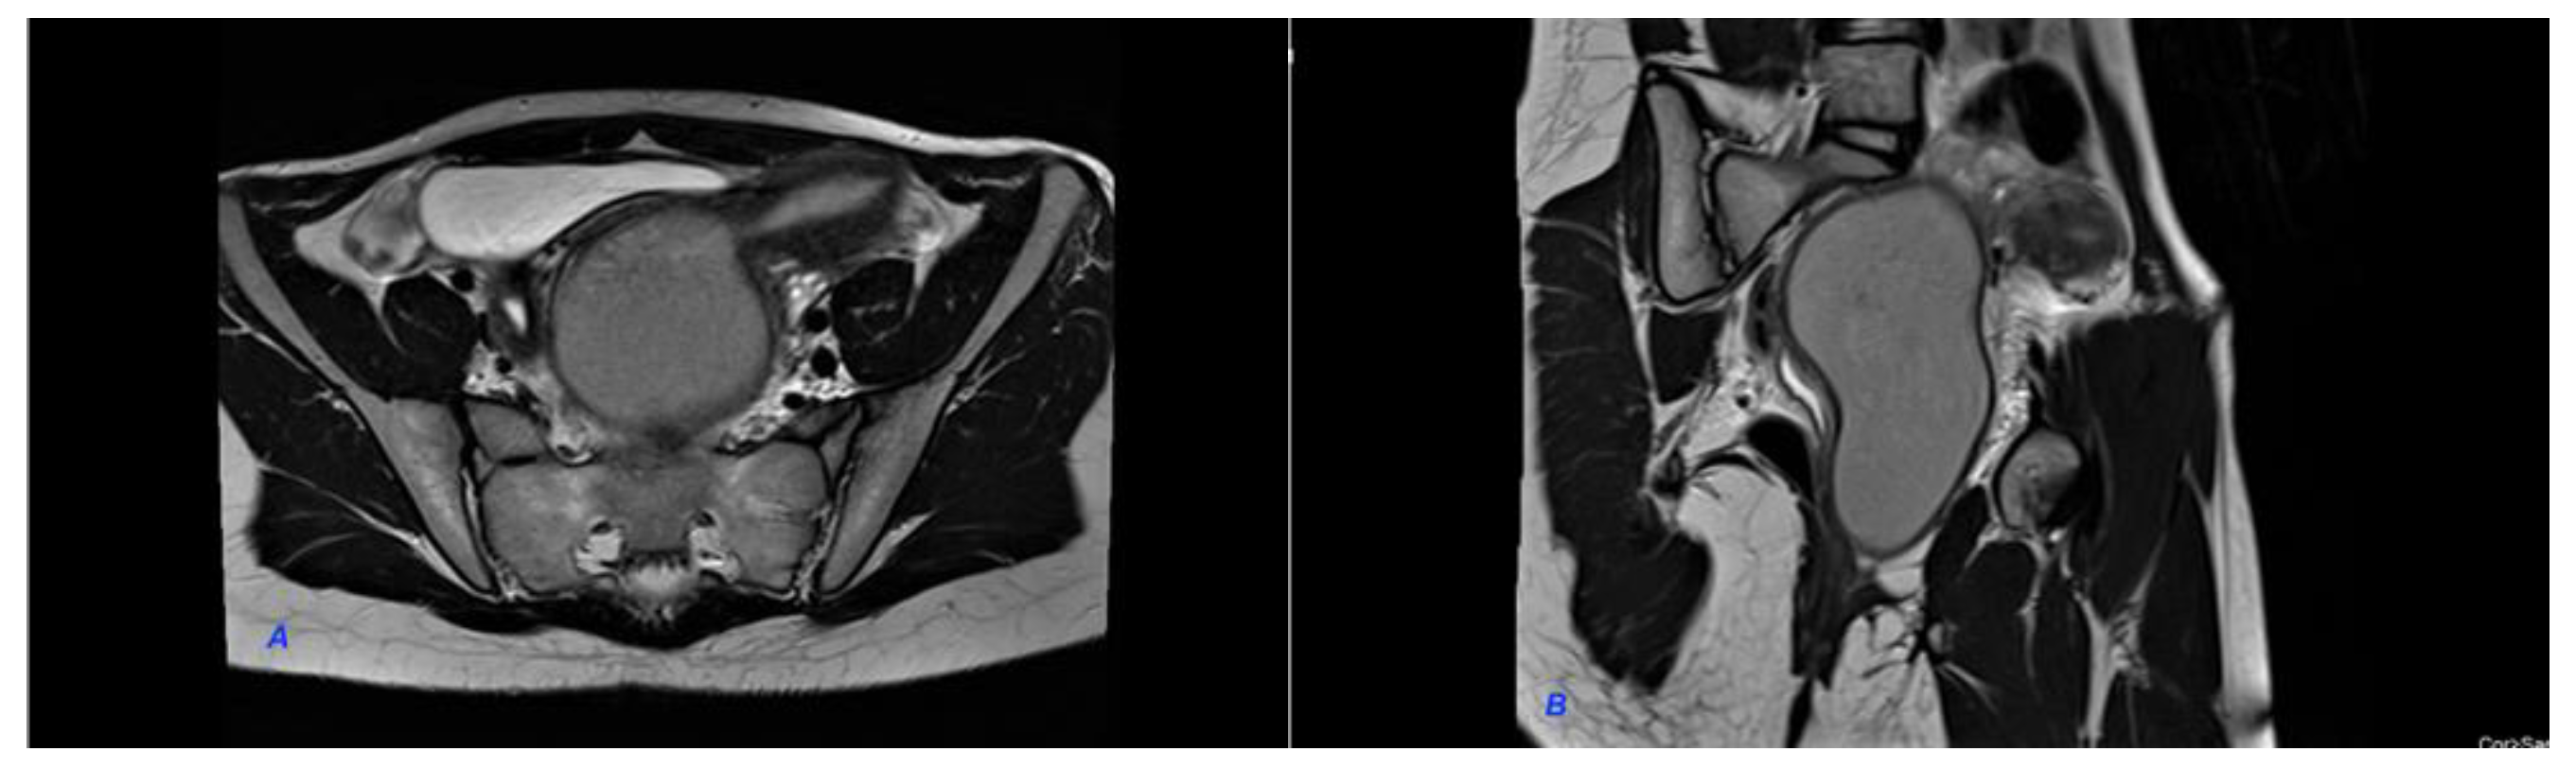

We present a case of HWWS diagnosed in our department in a 16-years-old girl who presented for severe left-lower quadrant pain, nausea, and urinary symptoms. Her menarche started the year before presentation, and monthly bleeding was regular; lasting 4 days; and was accompanied by increasing abdominal pain, nausea, urinary symptoms, and sometimes vomiting. She was not sexually active. During her first gynecology referral from another institution, she was recommended contraceptive pills for severe dysmenorrhea, which she refused. In the first visit in our hospital, the physical examination of the abdomen revealed mild abdominal tenderness of the left lower abdominal quadrant. Abdominal ultrasound (US) was performed but was considered not sufficiently informative; we only observed a voluminous cystic mass corresponding to hematocolpos. Therefore, after a careful explanation of the procedure and counseling, the girl and her parents decided to accept trans-rectal US examination. This revealed a didelphys uterus with a mild hematometra of the left hemiuterus, normal right hemiuterus and an impressive left-side collection, inferior and in connection with the left hemiuterus, corresponding to a hematocolpos. Both ovaries were present and of normal aspect and size (Figure 1). To better describe the findings and in view of the frequent association of congenital anomalies of the reproductive system with renal anomalies, an MRI was recommended and performed. The pelvic MRI showed two clearly separated hemiuteri (didelphys uterus), with mild left hematometra and normal right hemiuterus, mild left hematosalpinx, and an impressive left hemivagina, connected to the left hemiuterus, distended by a content whose signal was similar to methemoglobin, suggesting an obstructed hematocolpos (Figure 2A,B). Blood analysis was within normal range, except CA 125, which measured 89, 62 u/mL (more than the normal range for that age).

Figure 1. Transrectal US showing an impressive left hematocolpos and didelphys uterus with a mild hematometra of the left hemiuterus.